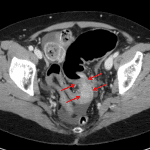

Age: 69

Sex: Female

Indication: Abdominal pain and distension

Findings

- Gaseous distension of the descending and sigmoid colon, measuring up to 6.5 cm in diameter

- Large stool burden in the cecum and ascending colon

- Small bowel loops appear decompressed

- No evidence of free subdiaphragmatic air

- Right upper quadrant surgical clips

- Mild dependent atelectasis in the visualized lung bases

Diagnosis

- Obstructing colon cancer

Findings concerning for large bowel obstruction at the level of the distal sigmoid colon. Recommend CT for further assessment.

Large proximal colonic stool burden. Small bowel loops appear nondistended.

No evidence of pneumoperitoneum.